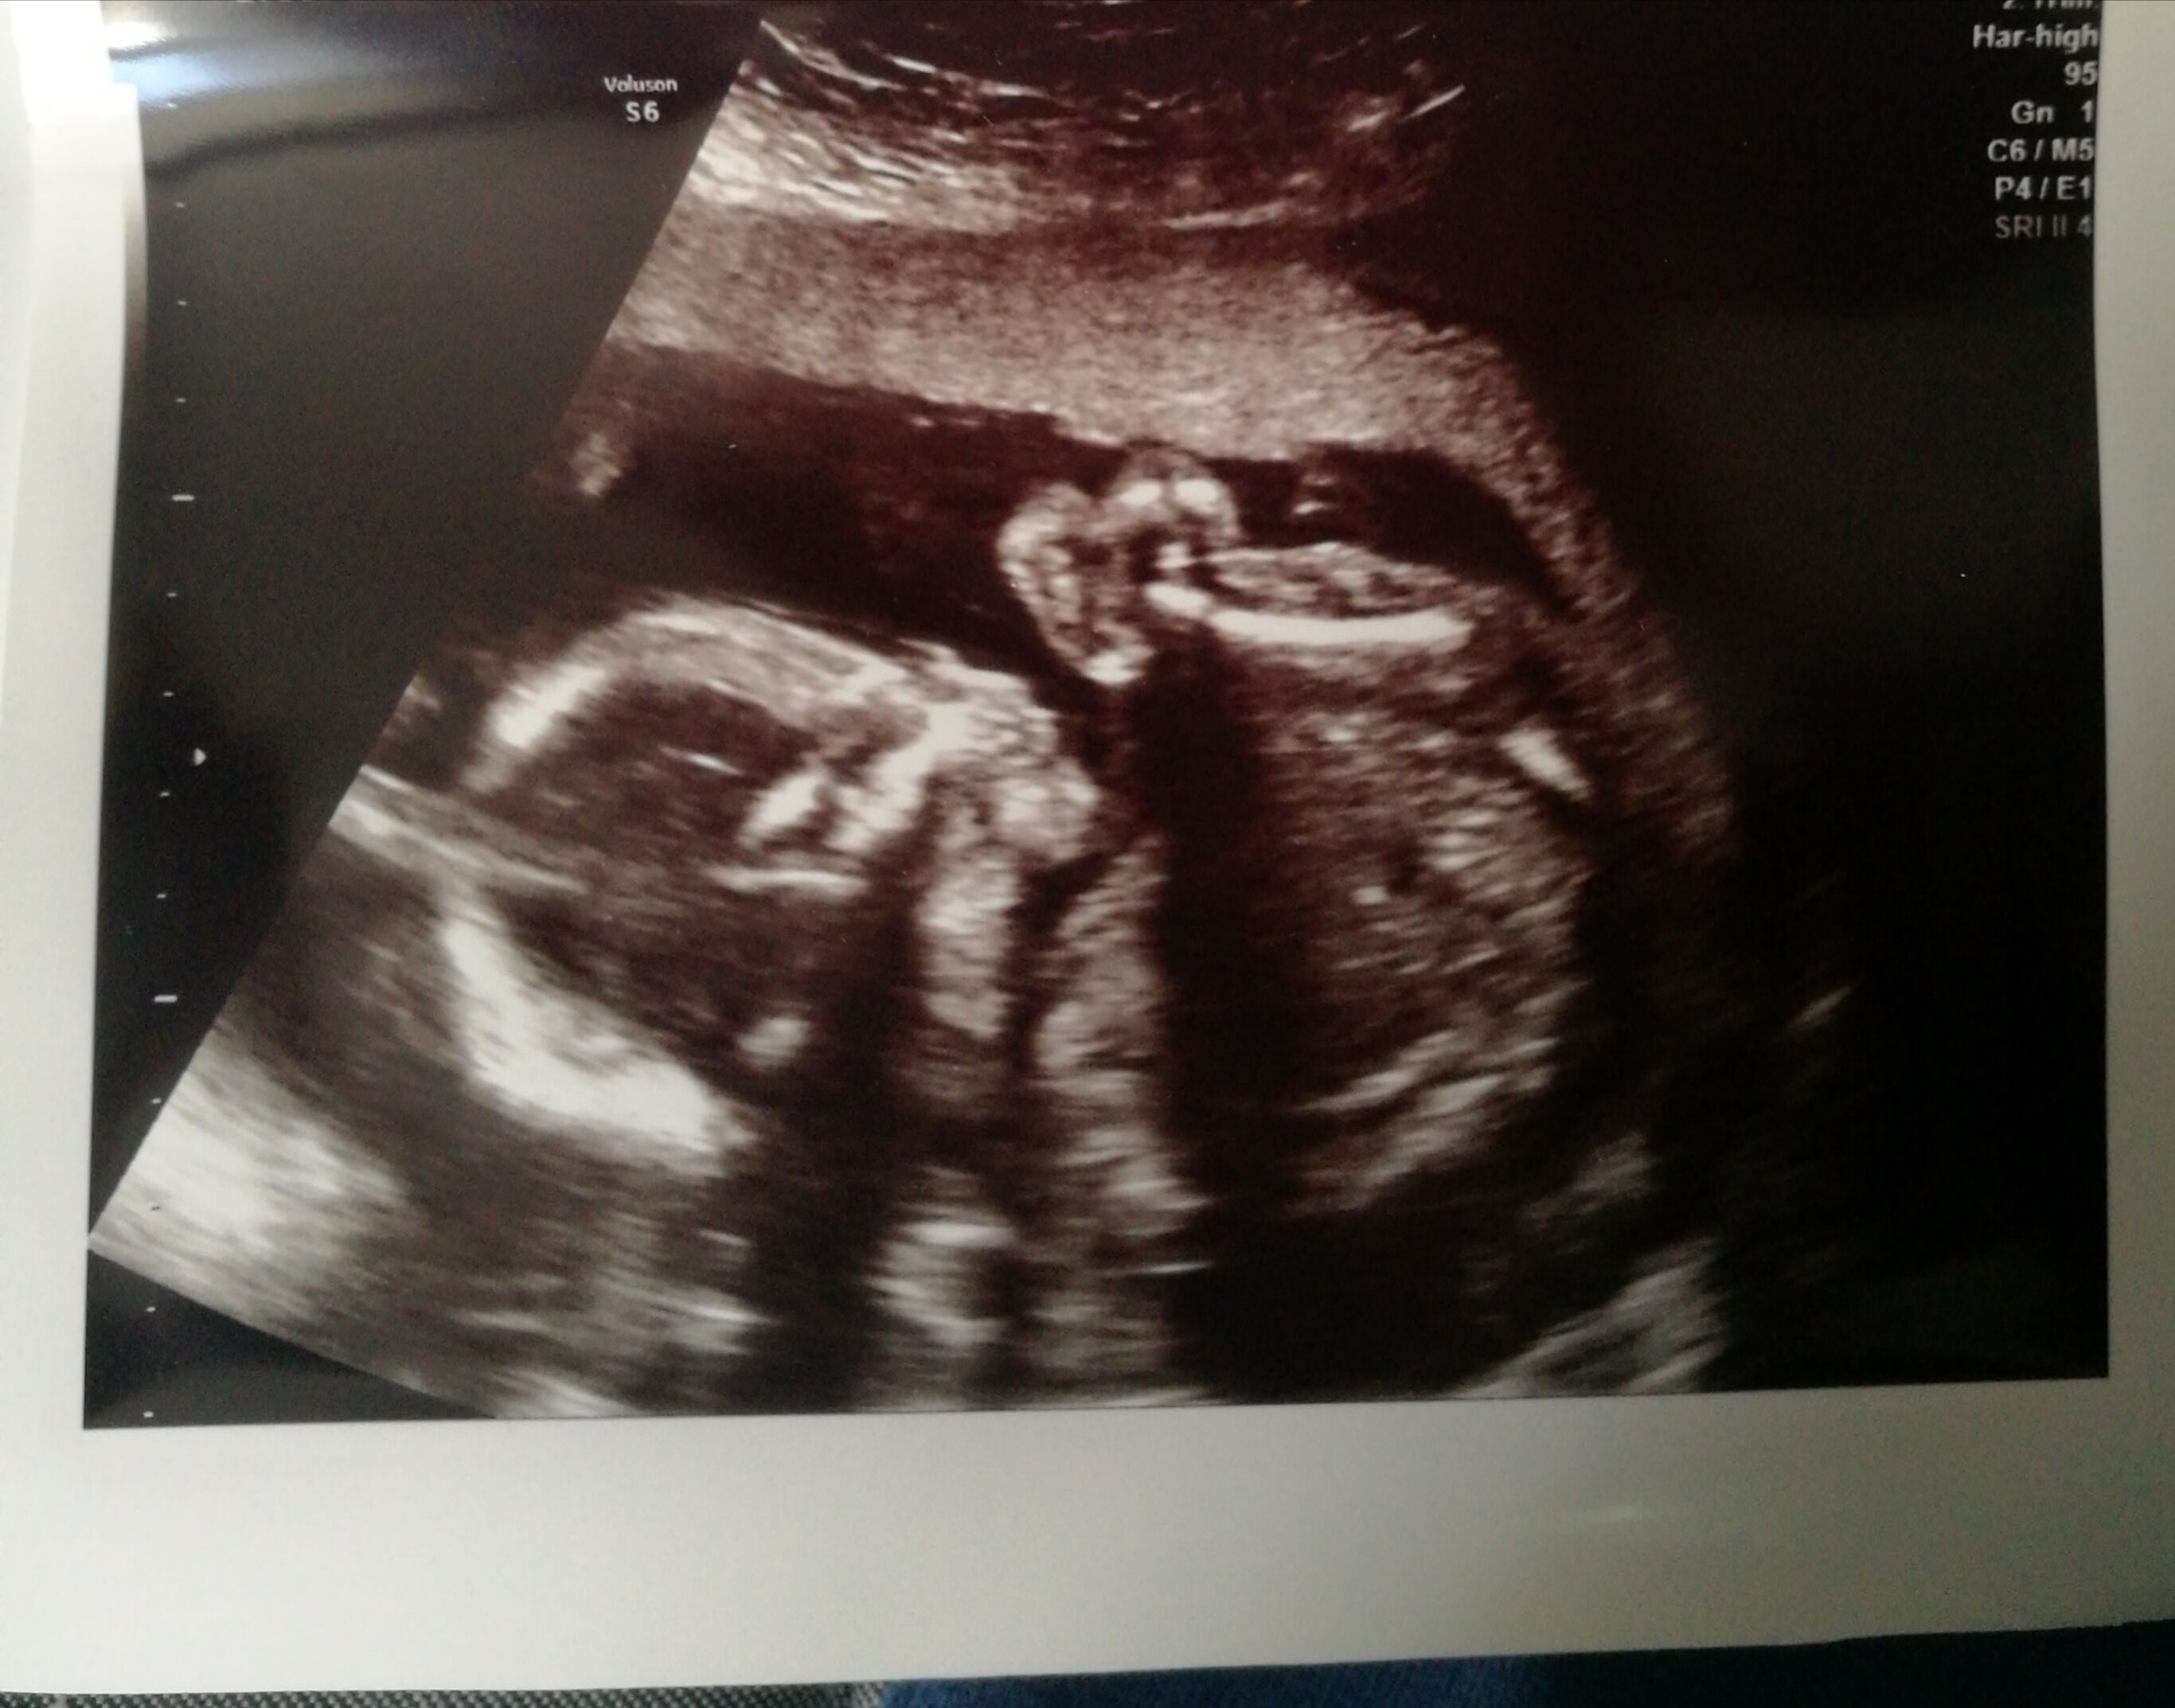

Gratulacje,który to tydzień?Forumowe ciocie, mam przyjemność poinformować, ze na połówkowych wszystko super ❤ maluch ma 409 gram i wszystkie narządy na swoim miejscu ❤❤❤

A to nie jest tak, że waga jest szacowana z długości?U nas dzisiaj 21+1 ❤ ja chodzę prywatnie, więc wagę mi na kazdej wizycie podaje na wydruku